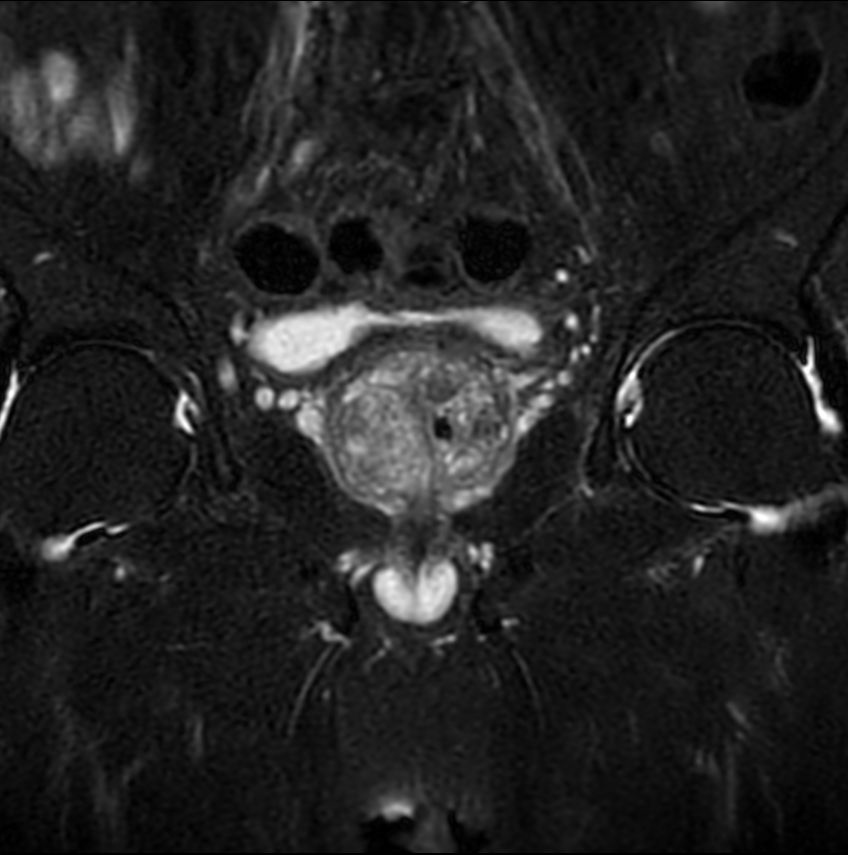

T1w FFE mDIXON XD- Compressed SENSE